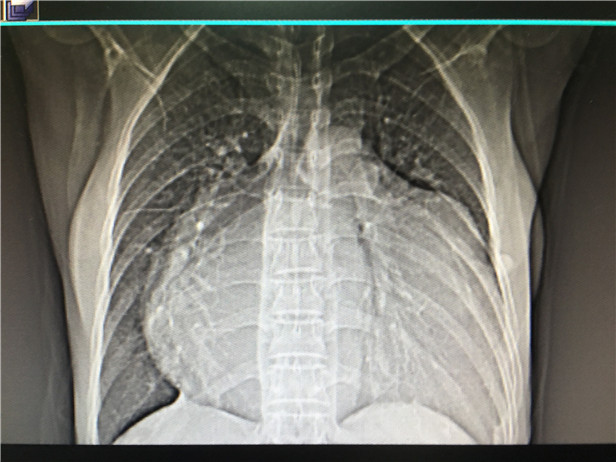

(术前的心脏照片)

意识到严重后,夫妻俩才又赶往黎平县中医院进行检查。这次,诊断结果连医生都被吓了一跳,“她的心脏是正常人的2倍,膨胀得像足球一样大,几乎占满了左右胸腔,情况十分危急,必须立即转院接受治疗。”医生们建议道。

血汗管外科主治医生吴昊告诉记者说,由于患者的病情拖延了12年,术前检查发现其左房内径为80mm(正常值20—33)可见,心房几乎增大了一倍,情况非常危急,手术难度非常大,最坏的结果很有可能患者无法走下手术台。